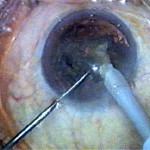

FINAL CLEANUP